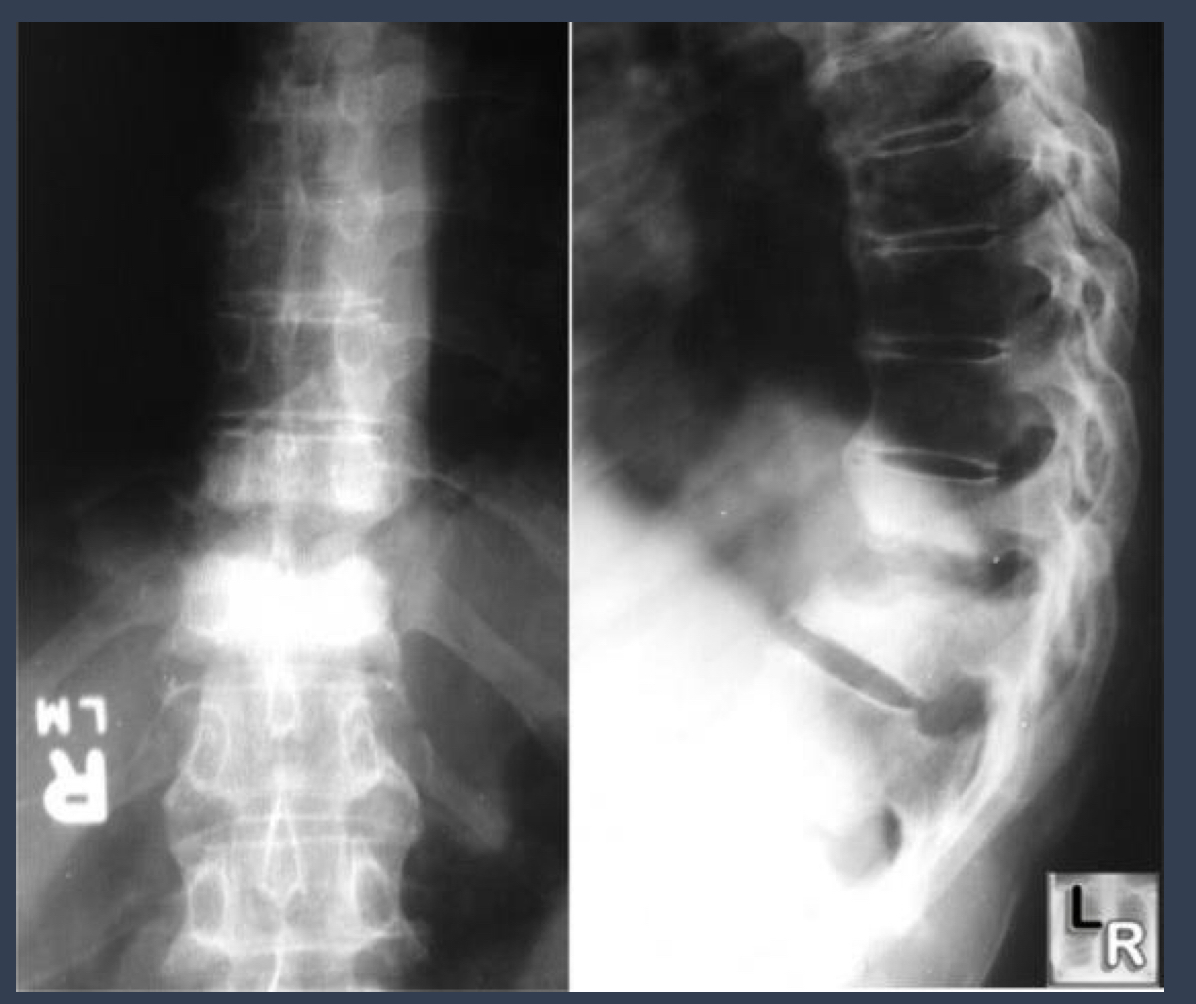

what is this?

spondylodiscitis

how is this spread?

hematogenously